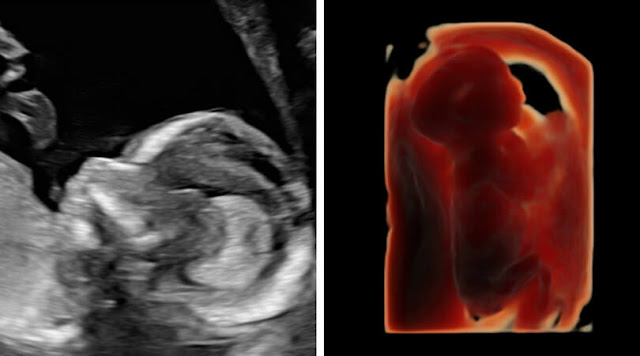

Take a look at the video if you want to see a super cute 16 week update with a 4D video clip! Due to my high risk status (trisomy 13, antiphospholipid syndrome, and cholestasis in the past), I get to go in for ultrasounds every 3-4 weeks.

I am 16 weeks today, and this week I got to go in for an early anatomy scan. The doctors warned me that we probably wouldn't see much, as it was just too early. Boy were they wrong, and they were so excited about it.

At this early anatomy scan we could see so many things. Baby William is developing perfectly so far and passing every test with flying colors.

The ultrasound technician even gave me a special surprise and did a 4D video clip. She let it run live for quite some time and I just got to see him wiggle around. It was precious and made my day. Tears happen every single ultrasound LOL!